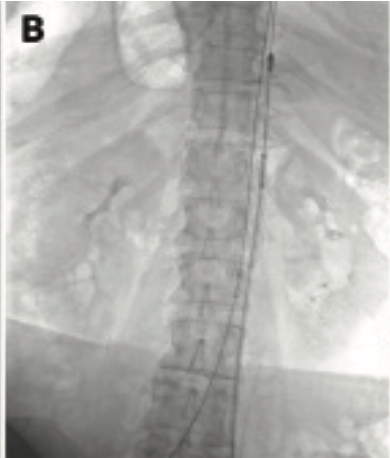

The FlowTriever System was advanced over the guidewire from the right popliteal vein access into the IVC beyond the thrombus and the FlowTriever disks were deployed for embolic protection. The ClotTriever sheath was then placed into the left popliteal access and then the ClotTriever catheter was advanced beyond the thrombus (Figure 3B). The coring element and collection bag were deployed, and the catheter was retracted toward the access site to capture and extract the thrombus.